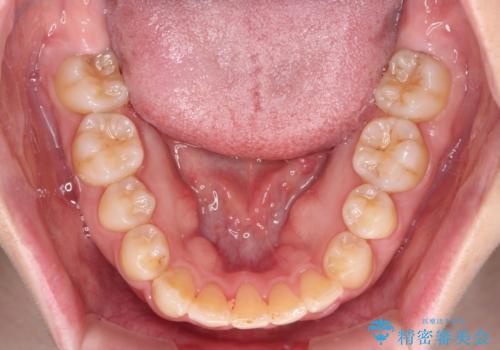

- 右上の八重歯と、左下八重歯を抜いてしまったことを気にして来院された患者様です。

下顎は既に犬歯を1本抜歯しているため、上顎右側第一小臼歯を抜歯し、ワイヤー装置にて歯列を整えることとしました。